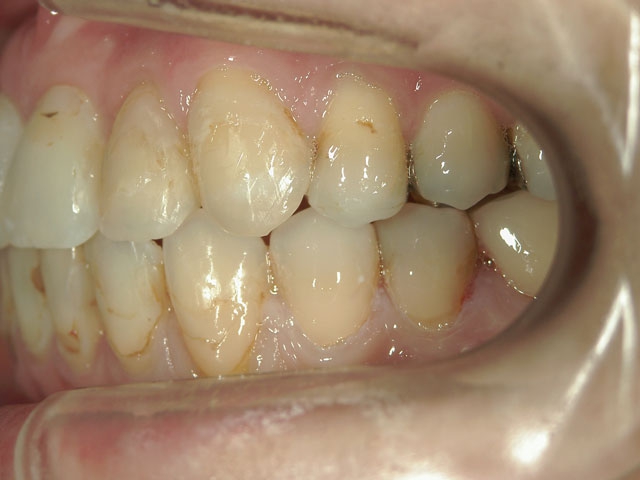

矯正歯科 治療前矯正歯科 治療前

28歳女性 浜松市中区在住

治療期間2年6ヶ月

矯正歯科 治療前 外科手術併用(コルチコトミー)、非抜歯